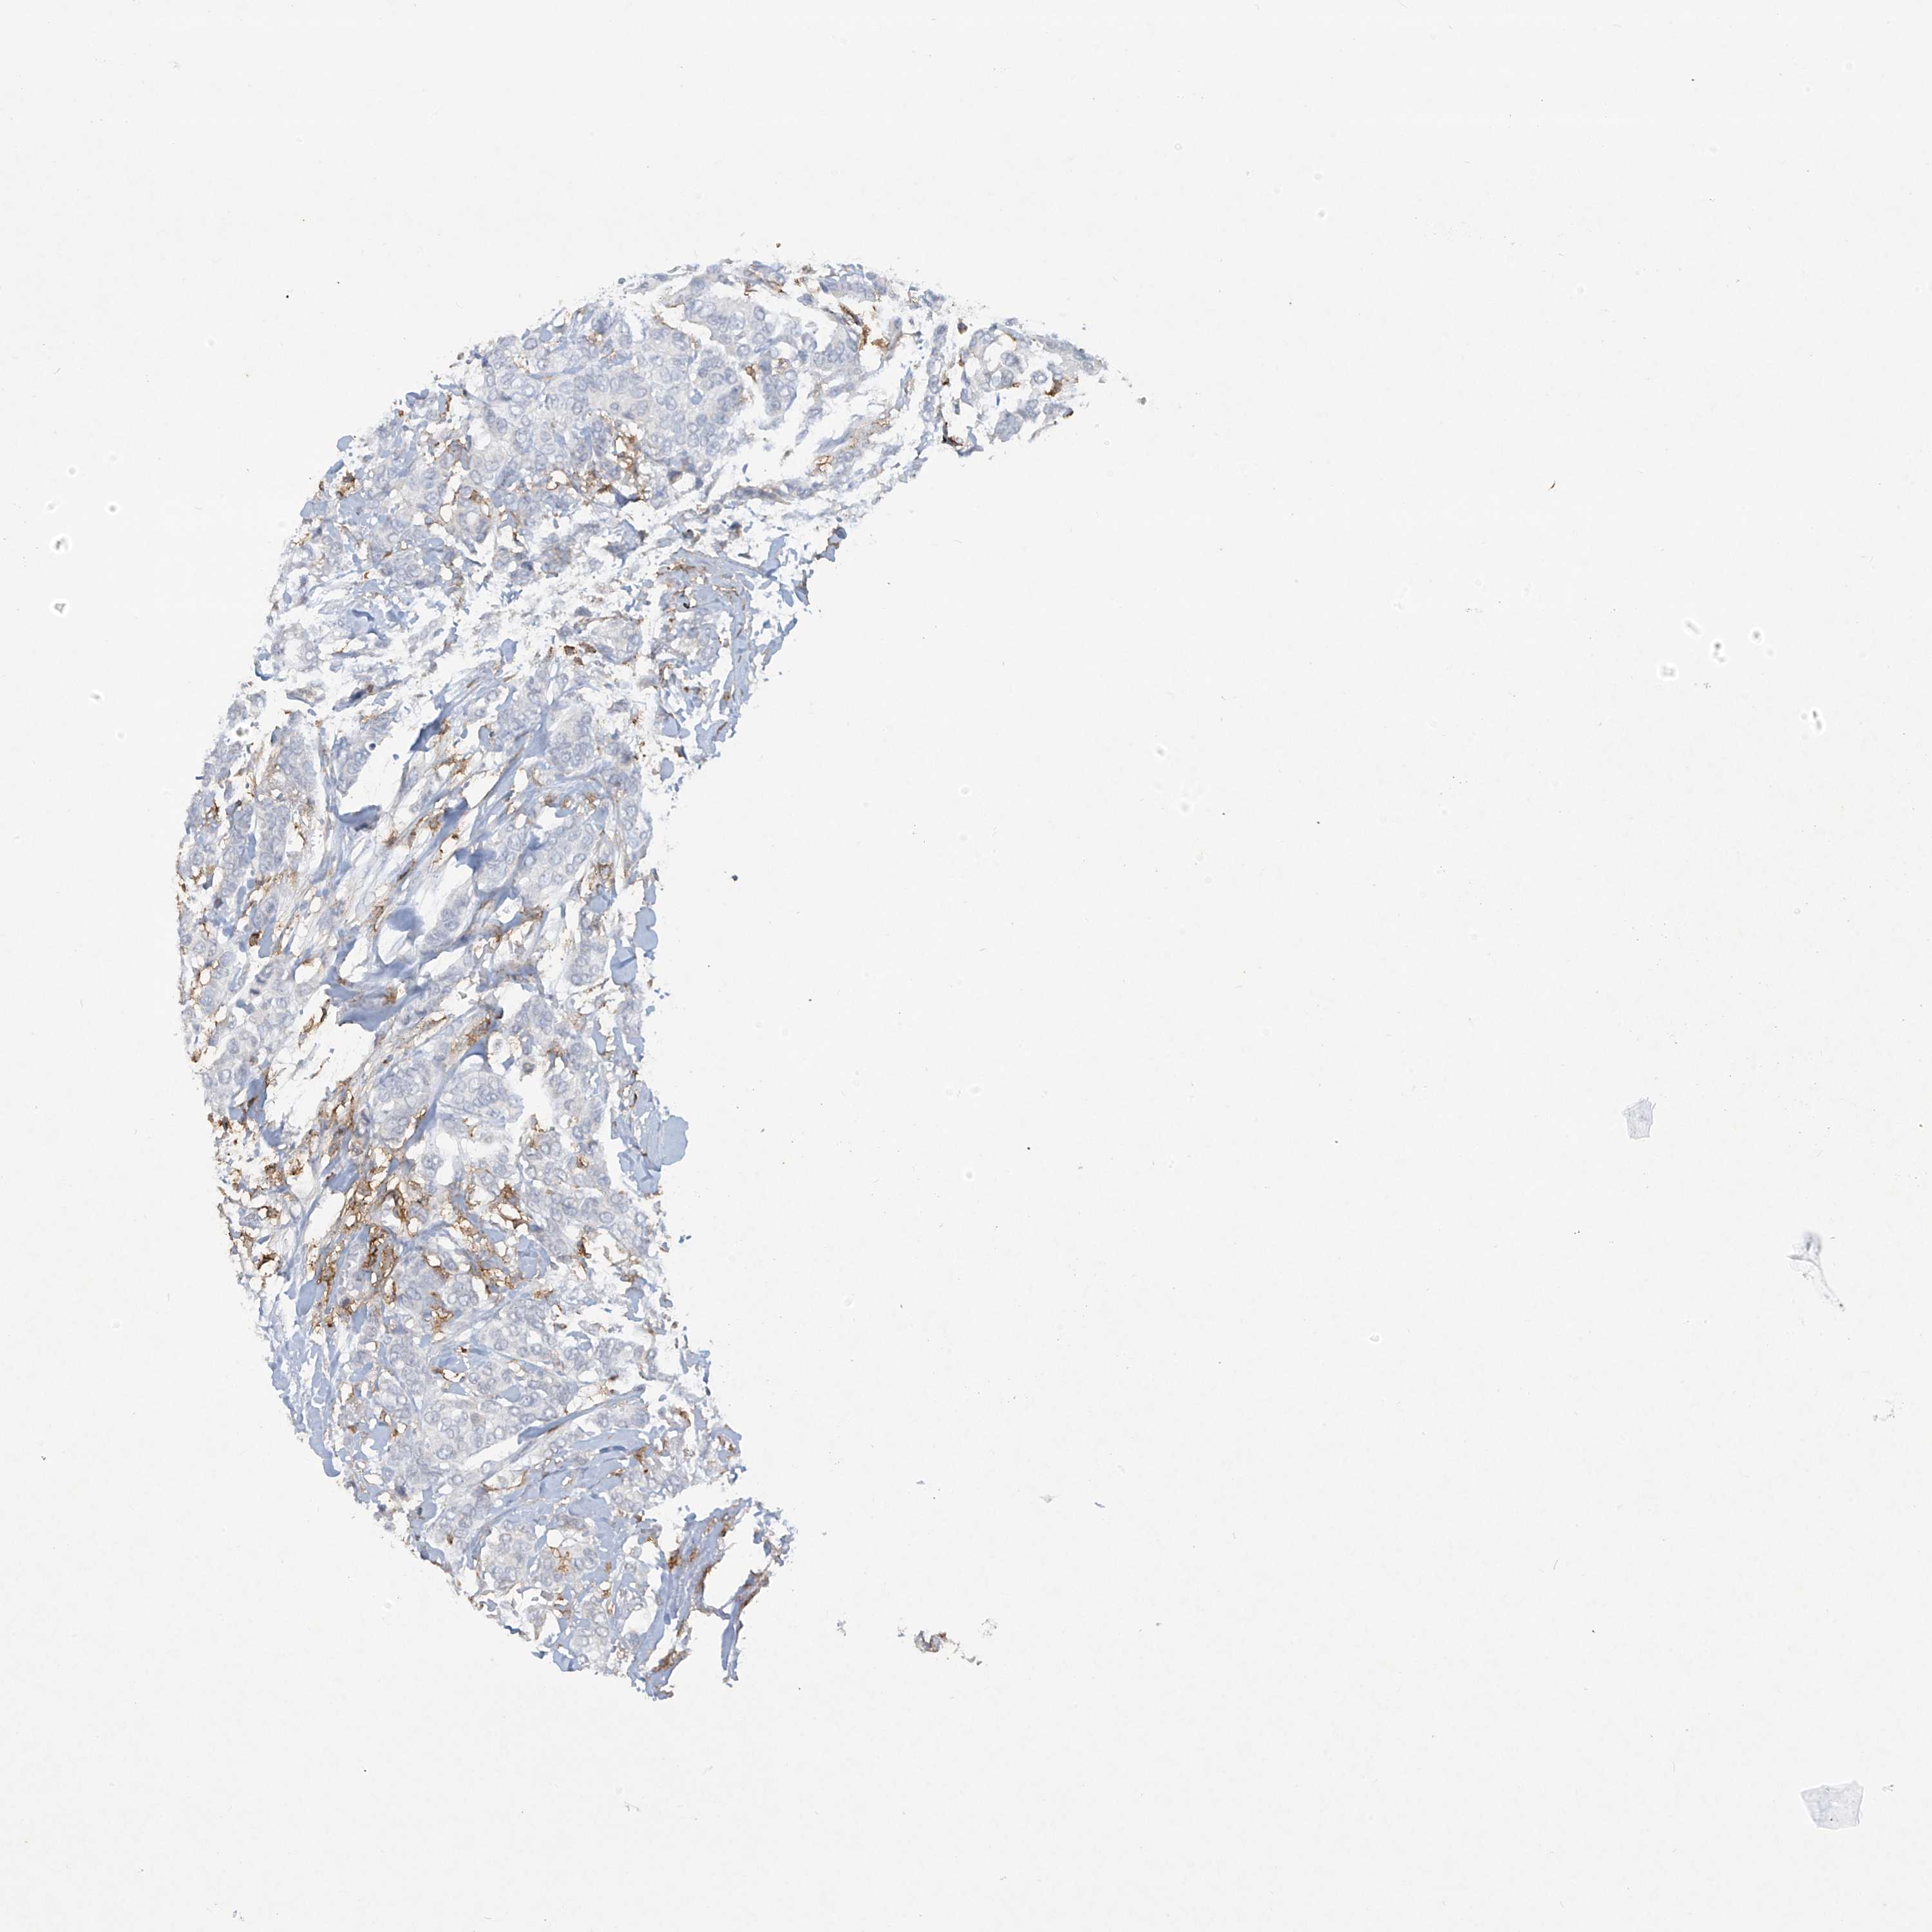

BRCA TCGA BRCA VALIDATION PROTEIN EXPRESSION

ANTIBODIES

AND

VALIDATION